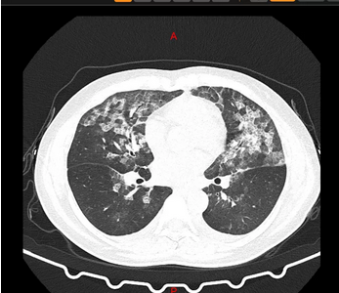

近日,郑州的张女士和王女士患了同一种“病”,她们感到头晕、乏力,遂到郑州市中心医院就诊。该院医生发现,两人的肺部CT均呈毛玻璃影,与新冠肺炎的表现基本上一模一样,然而二人并没有发烧及咳嗽、咳痰、呼吸困难等症状。

医院当即按照留观处置,等一切安置妥当后,问题又出现了。从CT影像上看虽然非常像新冠肺炎表现,但医生反复追问患者病史了解到,她们并没有新冠肺炎患者接触史,也未去过武汉,小区也没有确诊的患者,她们的症状表现和血象并不符合新冠肺炎……这一度让医生们非常纳闷。

正当大家毫无头绪之时,该院呼吸与危重症医学科主任发现了端倪。原来,两位女士居家期间,因为害怕感染新冠肺炎,每天定时在家喷洒高浓度84消毒液,又没有开窗通风,从而引起过敏性肺泡炎。所幸,经过3天的抗过敏治疗后,二人复查胸部CT,影像基本恢复正常。

过敏性肺泡炎治疗前与治疗后CT影像